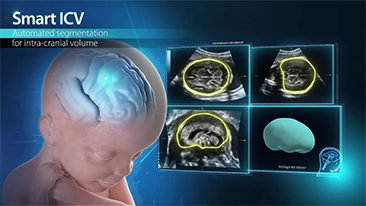

Geburtshilfe